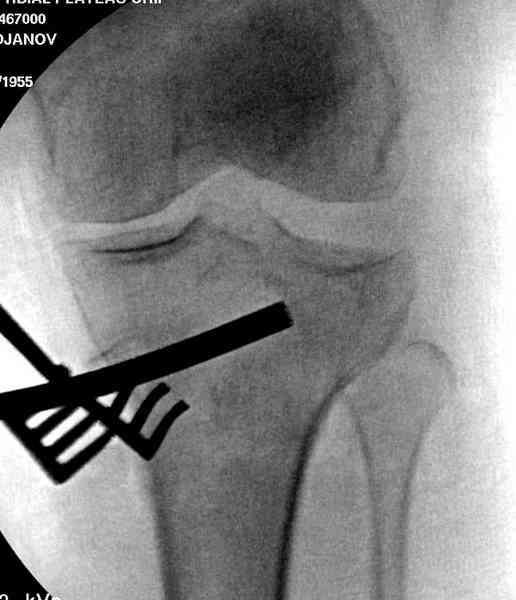

центральная импрессия, а при ипрессии с краевым переломом - после приподнимания импрессии опорная (Butress) пластина, как на снимке.